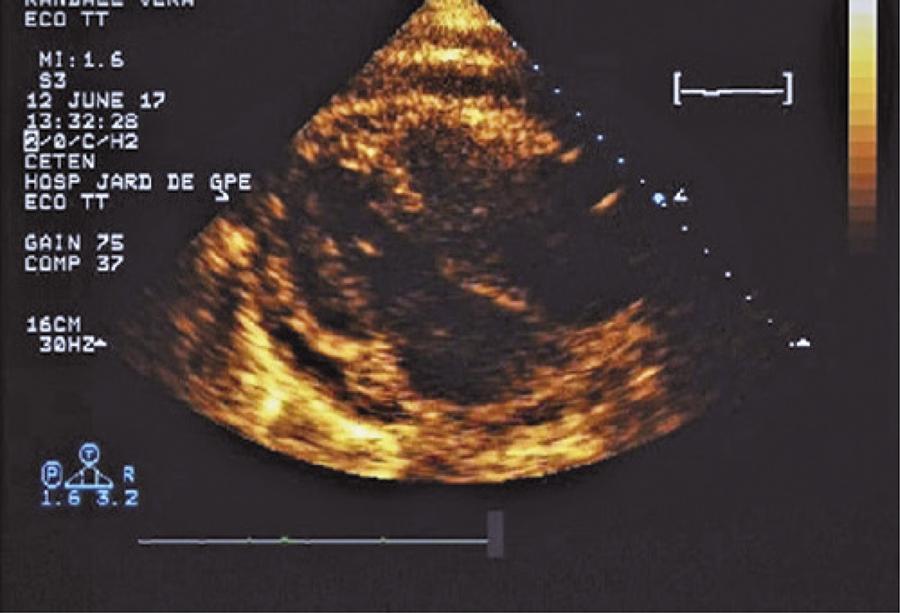

Figura 2

Derrame pericárdico observado pelo ecocardiograma.